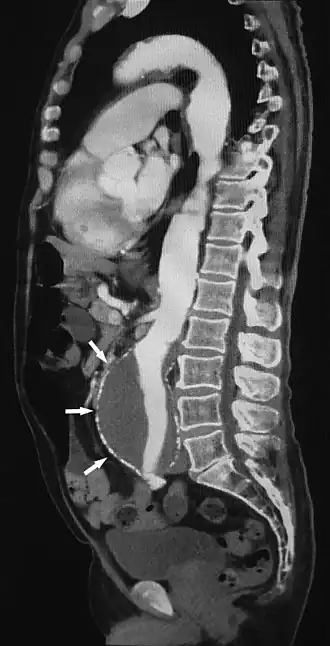

Sagittal thin slice of a computed tomography angiography abdominal aortic aneurysm (AAA) (arrows)

CTA can be used in the chest and abdomen to identify aneurysms in the aorta or other major blood vessels. These areas of weakened blood vessel walls that bulge out can life-threatening if they rupture. CTA is the test of choice when assessing aneurysm before and after endovascular stenting due to the ability to detect calcium within the wall.[3] Another positive of CTA in abdominal aortic aneurysm assessment is that it allows for better estimation of blood vessel dilation and can better detect blood clots compared to standard angiography.[4]

CTA is used also to identify arterial dissection, including aortic dissection in the aorta or its major branches. Arterial dissection is when the layers of the artery wall peel away from each other; this causes pain and can be life-threatening. CTA is a quick and non-invasive method of identifying dissections and can show the extent of the disease and if there is leakage.[4]